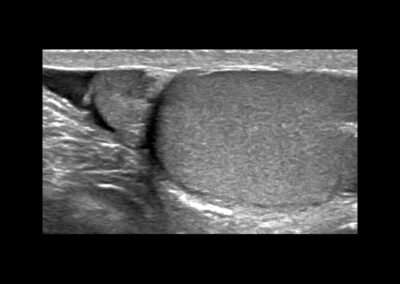

Eine genaue Anamnese und klinische sowie Ultraschalluntersuchung sind die Voraussetzungen für die richtige Diagnose. Immunsuprimierte Patienten (HIV) oder Patienten mit vorheriger Tuberkulose müssen erkannt werden. Die Urinuntersuchung kann einen Schlüssel für die mögliche Ursache geben. Die Symptome der Nebenhodenentzündung können innerhalb von 10 Tagen verschwinden, jedoch kann es bis zu 6 Wochen dauern, bis die Hoden sich wieder normal anfühlen. Die Spermienqualität kann sich vermindern. Das kann allerdings erst mindestens 6 Wochen nach einer Heilung festgestellt werden.

© Dr. Aref Elseweifi / masculine.de

Wenn die Gefahr einer Vereiterung droht, werden wir Ceftriaxon oder Tobramycin verschreiben. Dabei ist eine Ultraschalluntersuchung alle 3-4 Tage erforderlich. - Hoden-Hochlagerung